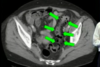

TOMOGRAFIA DE ABDOMEN COM CONSTRASTE VENOSO .

MASSA RETROPERITONEAL A DIREITA QUE COMPRIME AS VISCERAS A DIREITA , A QUAL NÃO INVADE AS ESTRUTURAS. PRESENÇA DE CAPTAÇÃO HETEROGENEA DO CONSTRASTE NA PERIFERIA

ASPECTO DE SARCOMA PERITONEAL.